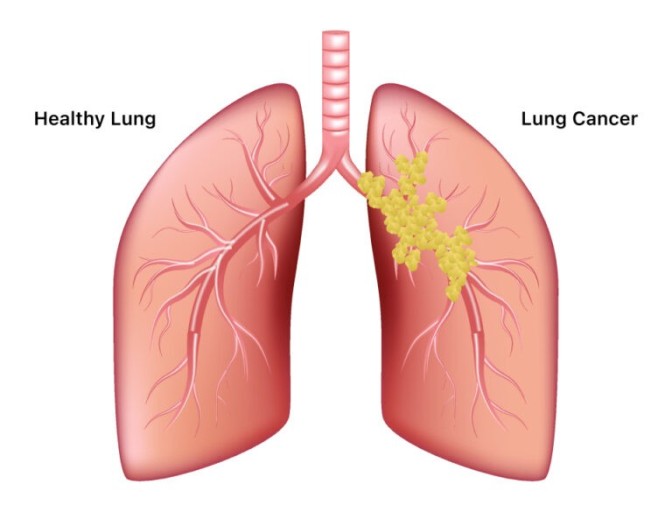

폐암은 초기 자각 증상이 뚜렷하지 않아 굉장히 진행된 상태에서 발견되는게 대부분입니다.. 그렇지만 조기 폐암은 매우 작은 부분만 절제해도 치료가 가능하며 생존율이 70~90%에 이른다.

폐암 증상에는 기침, 체중 감소 흉통, 혈담 즉 피가 섞인 가래, 호흡곤란 등이 있지만, 위 증상은 다른 폐 질환에서도 나타날 수 있는 증상으로 구분하기가 어렵다. 그리고 폐암 초기에는 특별한 증상이 없는 경우가 대부분이라서 최근 흡연뿐 아니라 미세먼지 등 여러가지 요인으로 폐암이 발생하는 경우가 많아 정기검진으로 조기에 발견하는 것이 중요며 폐암 검진을 위해서는 특히나 저선량 흉부 CT를 촬영하는 것이 좋다라고 전문가들은 말하고 있습니다..